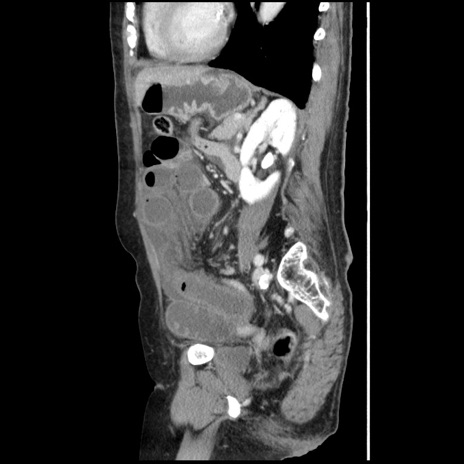

横断像

【症例】80歳代女性

【主訴】腹痛

【現病歴】8時間前から腹痛あり来院。

【既往歴】糖尿病、脂質異常症、子宮体癌にて子宮全摘術

【身体所見】意識清明・会話良好だが腹痛で苦悶様、全腹部にわたって反跳痛と圧痛あり

【データ】WBC 13600、CRP 0.14、LDH 224、CK 90